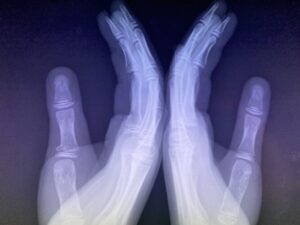

さわやか千葉県民プラザ(指骨骨折)